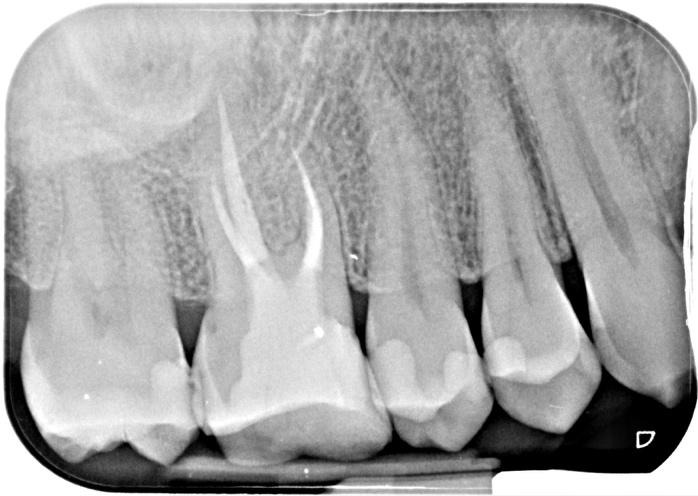

Pre-op IOPA and CBCT imaging

Key findings from CBCT Consultant radiologist’s report by JM Radiology:

- 5mm of broken instrument in mb1 mid/apical section of canal

- Unfilled mb2/confluent with mb1, this gave me three potential management strategies either direct bypass via mb1, bypass via mb2 due to shared portal of exit/ or removal

- Apical resorption mb/db roots

- Db portal of exit was not at the end of the root